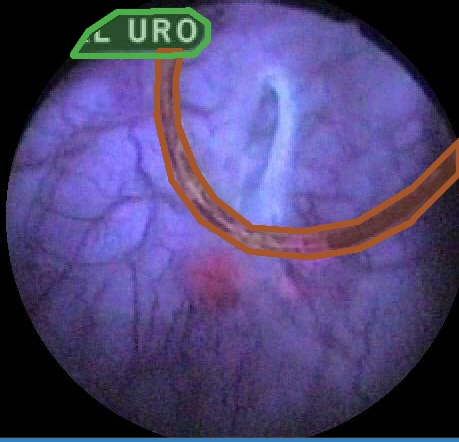

Examples for bounding box annotations for detection are shown in Fig. 2. It can be observed that while multiple boxes are annotated for several small specular areas; contrast, blur and instrument have relatively larger areas. Due to the overlap between two or more classes, the annotation by experts varied. This was minimized by following the detailed annotation protocol above. For semantic segmentation, a larger area mask was preferentially used to delineate locally very cluttered small specularity artifacts (see Fig. 3).